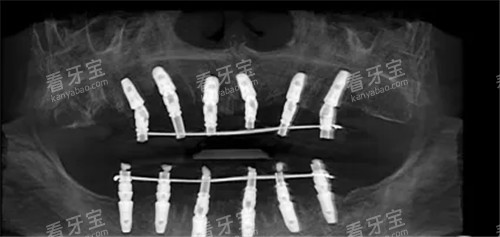

种植牙

种植牙对精度要求非常高,需要更准获取种植部位的骨质结构和邻牙情况。

因此,建议优先选择智能化扫描取模,它能提供更更准一些的数据,确保种植体的位置和角度更加更准,提高种植成功几率。

全口义齿

全口义齿需要完全贴合患者的口腔黏膜和颌骨形态,精度要求也很高。

智能化扫描能更准一些捕捉口腔的三维形态,制作出来的义齿贴合度更好,舒适度更高,建议优先选择。